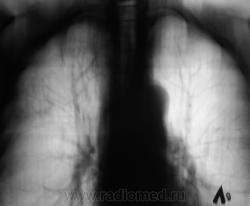

Пациент 4 месяца, по полной программе отлежал в областной конторе, ЦВК утвердило «инфильтративный». После выписки был направлен под надзор фтизиатра по месту жительства. Ниже иллюстрации после выписки.

Снимки сегодня.

Хорошая динамика, практически все рассосалось.

На мой взгляд на "семерке" еще дай-дай...